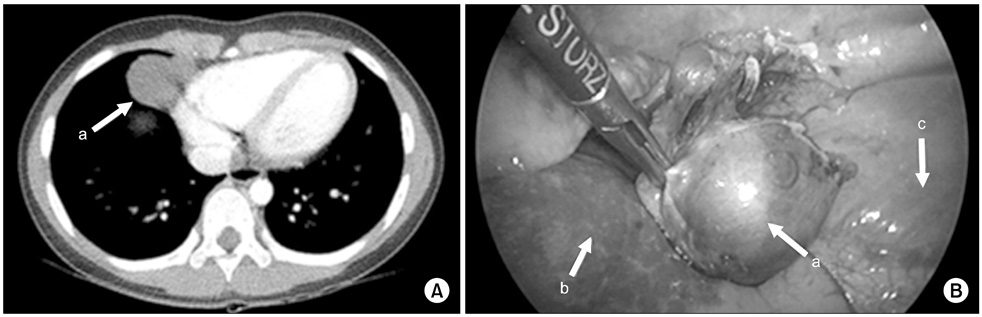

Fig. 7

Venous malformation. (A) There was mass at cardoiphrenic angle and it was suspected an inflammatory pseudo-tumor or congenital lung lesion like cystic lymphangioma on chest CT (3.0×3.6×2.3-cm-sized mass). (B) It was being originated from right pleura and was resected clearly. Arrows: a, mass; b, lung; c, diaphragm.

Fig. 7 Venous malformation. (A) There was mass at cardoiphrenic angle and it was suspected an inflammatory pseudo-tumor or congenital lung lesion like cystic lymphangioma on chest CT (3.0×3.6×2.3-cm-sized mass). (B) It was being originated from right pleura and was resected clearly. Arrows: a, mass; b, lung; c, diaphragm.